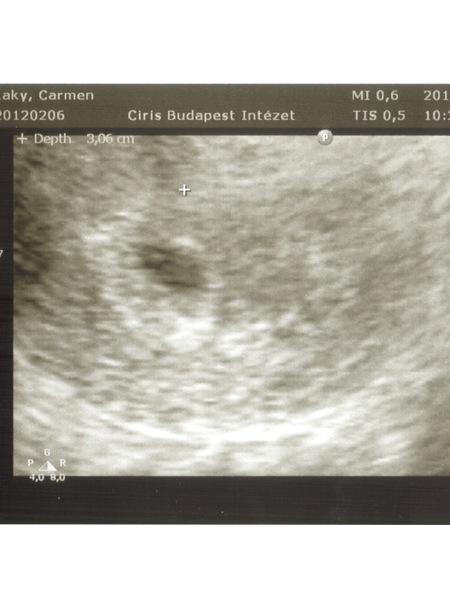

Beszkenneltem az UH képeket:) nem tudom, mennyi fog belőle látszani.

Kép

Kép [/img]

Süti, tök jó a két pöttyös kép, tényleg olyan, mint egy UHU :)

Gyönyörűek a pöttyeid! Örülök, hogy minden oké!